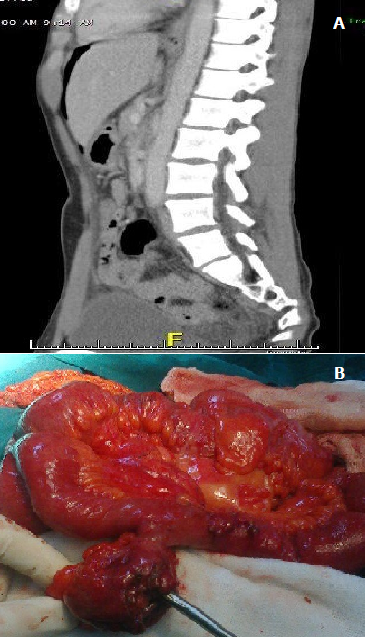

Le diverticule de Meckel est une affection rare qui touche 2% de la population générale. Le plus souvent asymptomatique, le diverticule de Meckel peut se manifester par des douleurs de la fosse iliaque droite mais il peut aussi se révéler parfois chez l'enfant ou l'adulte jeune par des complications : occlusion, infection dite diverticulite, hémorragie digestive basse.la perforation est le plus souvent la conséquence d'un corps étranger intradiverticulaire. Nous rapportons le cas d'un patient âgé de 43 ans admis en urgence pour un syndrome péritonéal dans les suites d'une contusion abdominal (piéton heurté par une voiture), le scanner abdominal avait objectivé un épanchement de moyenne abondance avec un pneumopéritoine (A). Au terme de cette étape clinique et radiologique l'existence d'une perforation d'un organe creux en particulier colique ou duodénale a été suspectée, l'hypothèse d'une perforation grélique était faible car cela ne s'associe pas à un pneumopéritoine après quelques heures dans les suites d'un traumatisme fermé de l'abdomen. L'exploration chirurgicale avait montré une péritonite stercorale par perforation d'un diverticule de Meckel (B) sans autres lésions associés; il a été réalisé une toilette péritonéale avec une résection du grêle emportant le diverticule, une double stomie a la Bouilly volkman au niveau de la fosse iliaque droite. Les suites immédiates étaient favorables, le patient a été repris 3 semaines plus tard pour rétablissement de la continuité digestive. L'examen anatomopathologique de la pièce avait confirmé l'existence d'un diverticule de Meckel perforé.